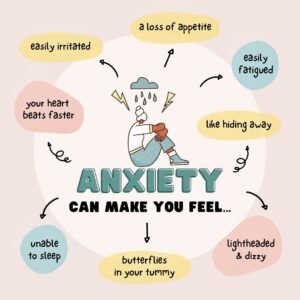

Anxiety